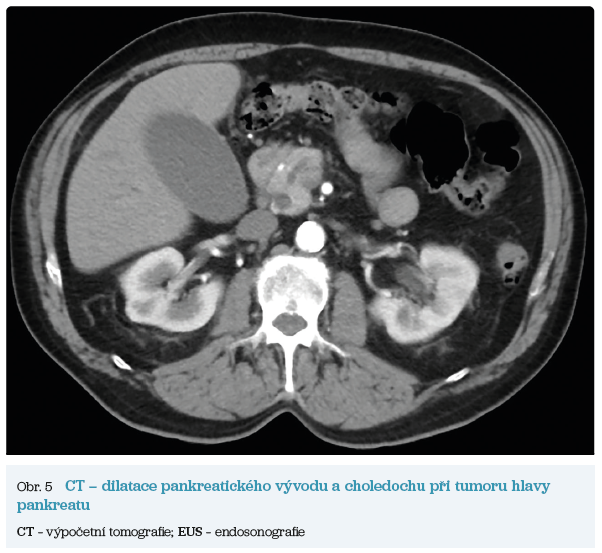

Několik studií se zabývalo AI asistovanou CT detekcí karcinomu pankreatu s AUC 0,79–0,99 %,6–8 tedy přesností porovnatelnou s přesností práce zkušeného radiologa. Stran časné detekce proběhla studie posuzující přesnost AI modelu v detekci karcinomu pankreatu v období 3–36 měsíců před prvními projevy onemocnění. Zařazeno bylo 155 pacientů s karcinomem pankreatu a 265 zdravých kontrol. AI model zde dosáhl AUC 0,98, což výrazně předčilo radiology, kteří při popisování stejných případů dosáhli AUC 0,66.9 Studie využívající DL model pro rozlišení zdravé slinivky od nálezu pankreatických neoplazií, tedy karcinomu pankreatu, intraduktální papilární mucinózní neoplazie (IPMN), serózních a mucinózních cystických neoplazií a solidní pseudopapilární neoplazie, byla prezentována s AUC 0,91, tedy opět odpovídající přesnosti popisu radiologa.10 Pro další vývoj a možné klinické využití bude potřeba přístupu k rozsáhlému archivu CT snímků karcinomu pankreatu, aby se ML modely mohly zdokonalovat. Další studie se věnovaly AI asistované diferenciální diagnostice. Ta bývá u lézí pankreatu velmi obtížná a pokrok v této problematice je tak velmi přínosný. Mezi nejzajímavější patří studie zabývající se rozlišením serózních a mucinózních cystadenomů s AUC 0,932.11 Další studie zkoumala úspěšnost rozlišení karcinomu pankreatu od zbytnění pankreatu při určitých formách chronické pankreatitidy (MFP – mass forming pancreatitis) s AUC 0,866.12 V další studii byla AI využita k rozlišení fokální autoimunitní pankreatitidy od karcinomu pankreatu s AUC 0,97.13 V rámci MR proběhlo několik studií, které se zaměřily na AI asistované zachycení a klasifikaci pankreatického karcinomu či IPMN. Studie klasifikující IPMN pomocí konvoluční neuronové sítě (CNN – convolutional neural network) byla schopna rozlišit dysplazii vysokého stupně od přítomnosti karcinomu se senzitivitou 76 %, specificitou 78 % a AUC 0,78.14 Další studie porovnávala AI modely CT a MR v predikci maligního IPMN. Výsledky ukázaly, že MR model s AUC 0,94 byl přesnější než CT model s AUC 0,864.15 S využitím PET/CT byl prozkoumán AI model rozlišující od sebe akutní pankreatitidu a karcinom pankreatu s AUC 0,9668.16 Výsledky AI v oblastech zobrazovacích metod jsou tak slibné. Dosahují minimálně přesnosti srovnatelné s radiologem a zejména v problematice časných karcinomů pankreatu člověka svojí přesností převyšují (obr. 1–5).